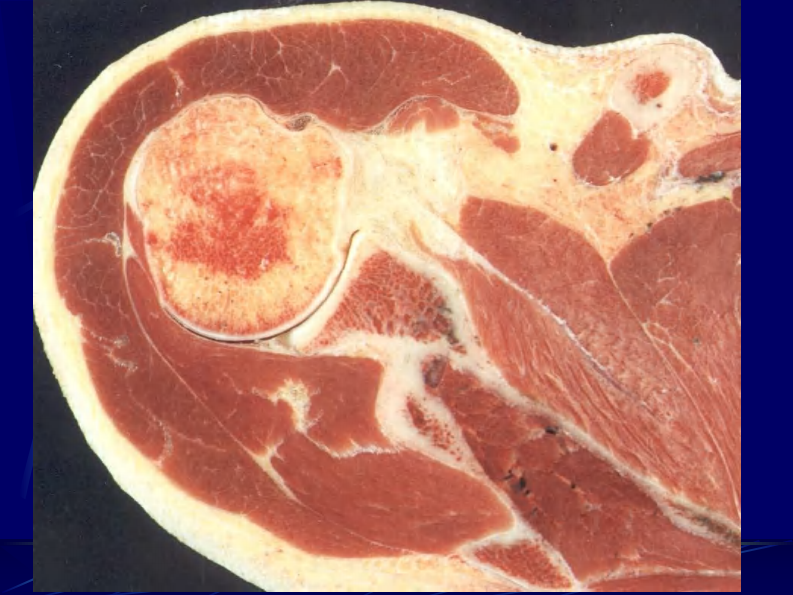

14 四肢断层解剖及CT、MRI.pdf